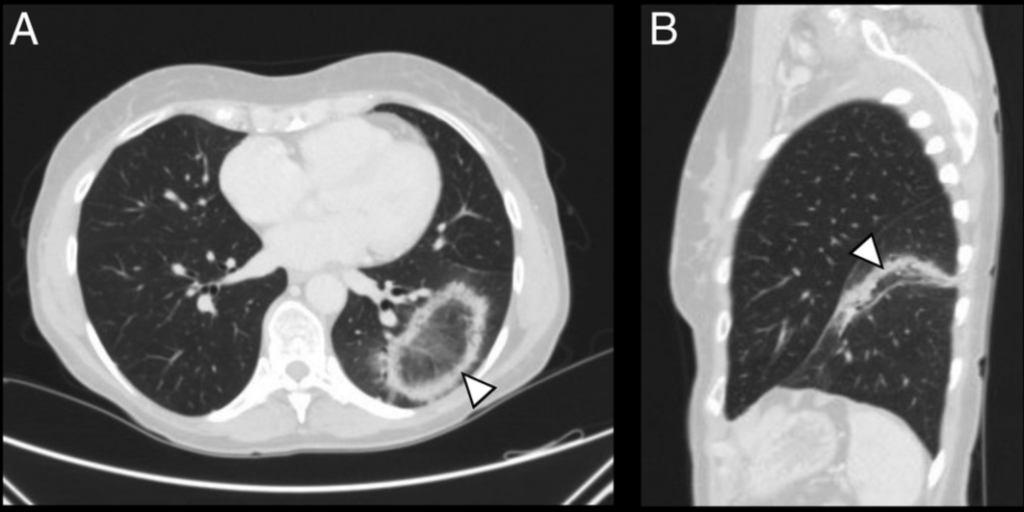

CASO 1

Donna di 40 anni, tosse secca, febbricola

TC torace senza mdc:

In quale condizione si riscontra questo segno radiologico?

Risposta esatta: D

COP:

- Consolidamenti periferici/subpleurici

- Distribuzione peribroncovascolare

- Infiltrati migranti

- “Reversed halo sign” (consolidamento periferico ad anello con centro a vetro smerigliato)

Il punto fine (quello che distingue il bravo radiologo)

- Non segue distribuzione lobare batterica

- Non dà distruzione parenchimale

- Può simulare neoplasia multifocale

- Spesso risponde drammaticamente ai corticosteroidi

Differenziale insidiosa

- Adenocarcinoma in situ

- Vasculiti

- Polmoniti eosinofile

- ARDS organizzativa

La migrazione delle lesioni nel tempo è un indizio molto forte.